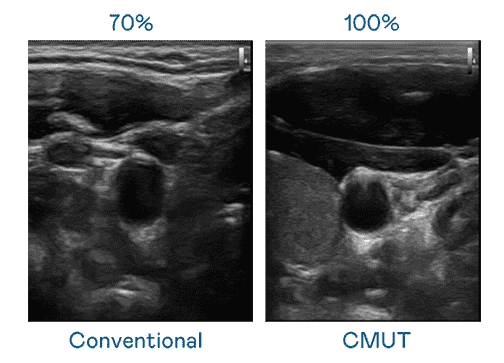

CMUT 技术是一种用电容式微机电元件来产生超音波讯号的技术。。。与传统 PZT 压电式技术相比,,,CMUT 频宽增加 30%,,更宽频的超音波讯号让影像解析度大幅提升,,,是实现高影像品质医疗超音波扫描、、促进精准医疗发展的关键技术。。。

大频宽带来超清晰影像

超音波影像的解析度高低,,,,首先取决于探头能发出的讯号频宽。。。彩运网 CMUT 可提供高清晰的超音波讯号,,,,提供高频宽、、、高灵敏度、、、、影像纹理细节更高的超音波影像,,,,协助医护人员缩短影像判读时间及利用精准的医疗影像进行诊断。。